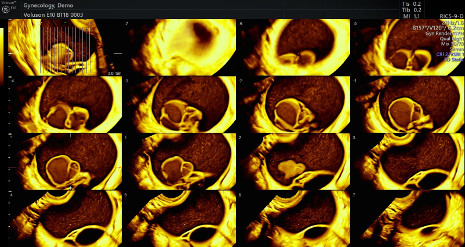

Todos los avances del ecógrafo VOLUSON E10 BT18 se aplican también a la salud de la mujer. Especialmente en el diagnóstico precoz de patología ginecológica, la posibilidad de realizar imágenes en 4d y multicorte permite la detección y estudio de quistes ováricos y diferenciar sin son benignos o malignos, diferenciar miomas uterinos respecto a sarcomas uterinos, entre otros.